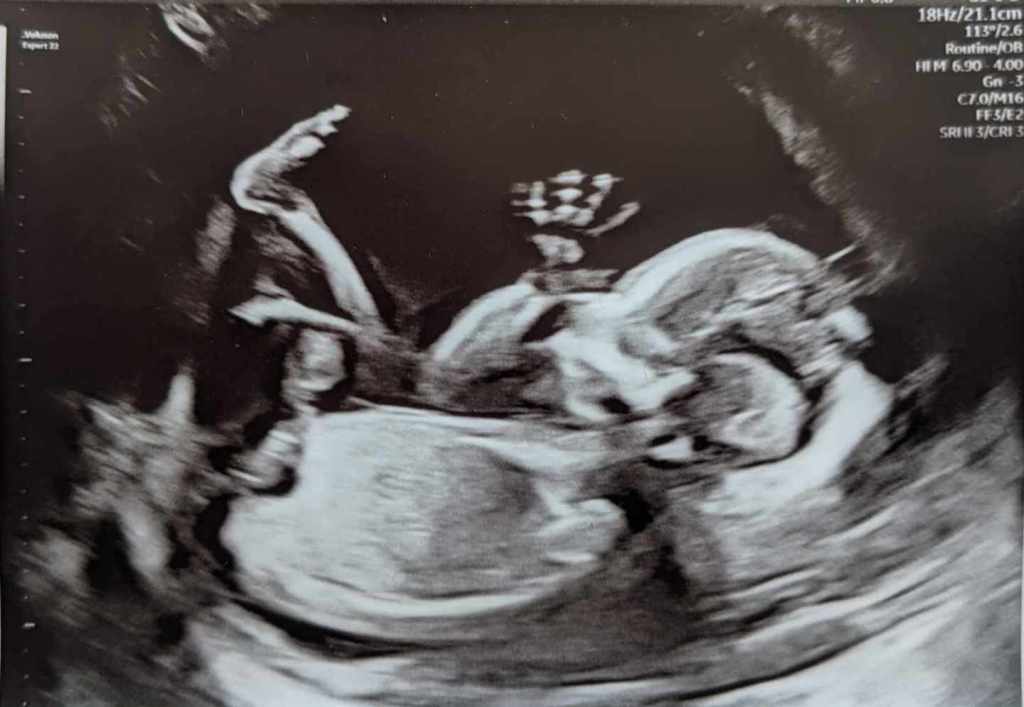

Ironically, one of the last times I was actually updating this blog, it was to share my musings about making the decision of whether or not to become a parent. Now I’m coming out of the woodwork to share that that decision has been made, quite conclusively, with a baby on the way in August of 2024!